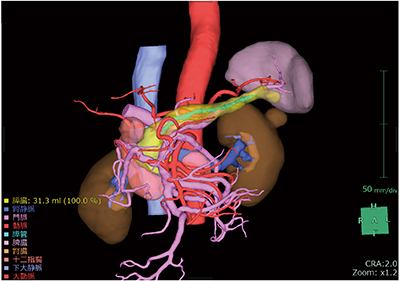

膵臓解析では,膵液の経路である膵管を自動で抽出する機能を搭載し,術前に膵管の位置を視覚的にとらえることができる。また,膵臓直交断面を表示することにより,指定位置での膵管の詳細な位置や膵実質断面の厚み,面積を計測することが可能である。加えて,ガイドライン1)で推奨されている門脈左縁での切除ラインの任意設定(図2)や,各膵腫瘍の位置に応じて腫瘍マージンを表示する機能(図3)を追加し,適切な切除ラインをプランニングするために必要な機能を提供する。切除ラインから残膵ボリューム(あるいは切除される膵臓ボリューム:図4)を算出し,体積評価も可能である。さらに,肝臓解析や腎臓解析と同様に,鏡視下シミュレータ(別途オプション必須)を連携して起動させることで,仮想内視鏡ビューを表示し,術前,術中に参照することができる(図5)。

図3 腫瘍マージン表示機能